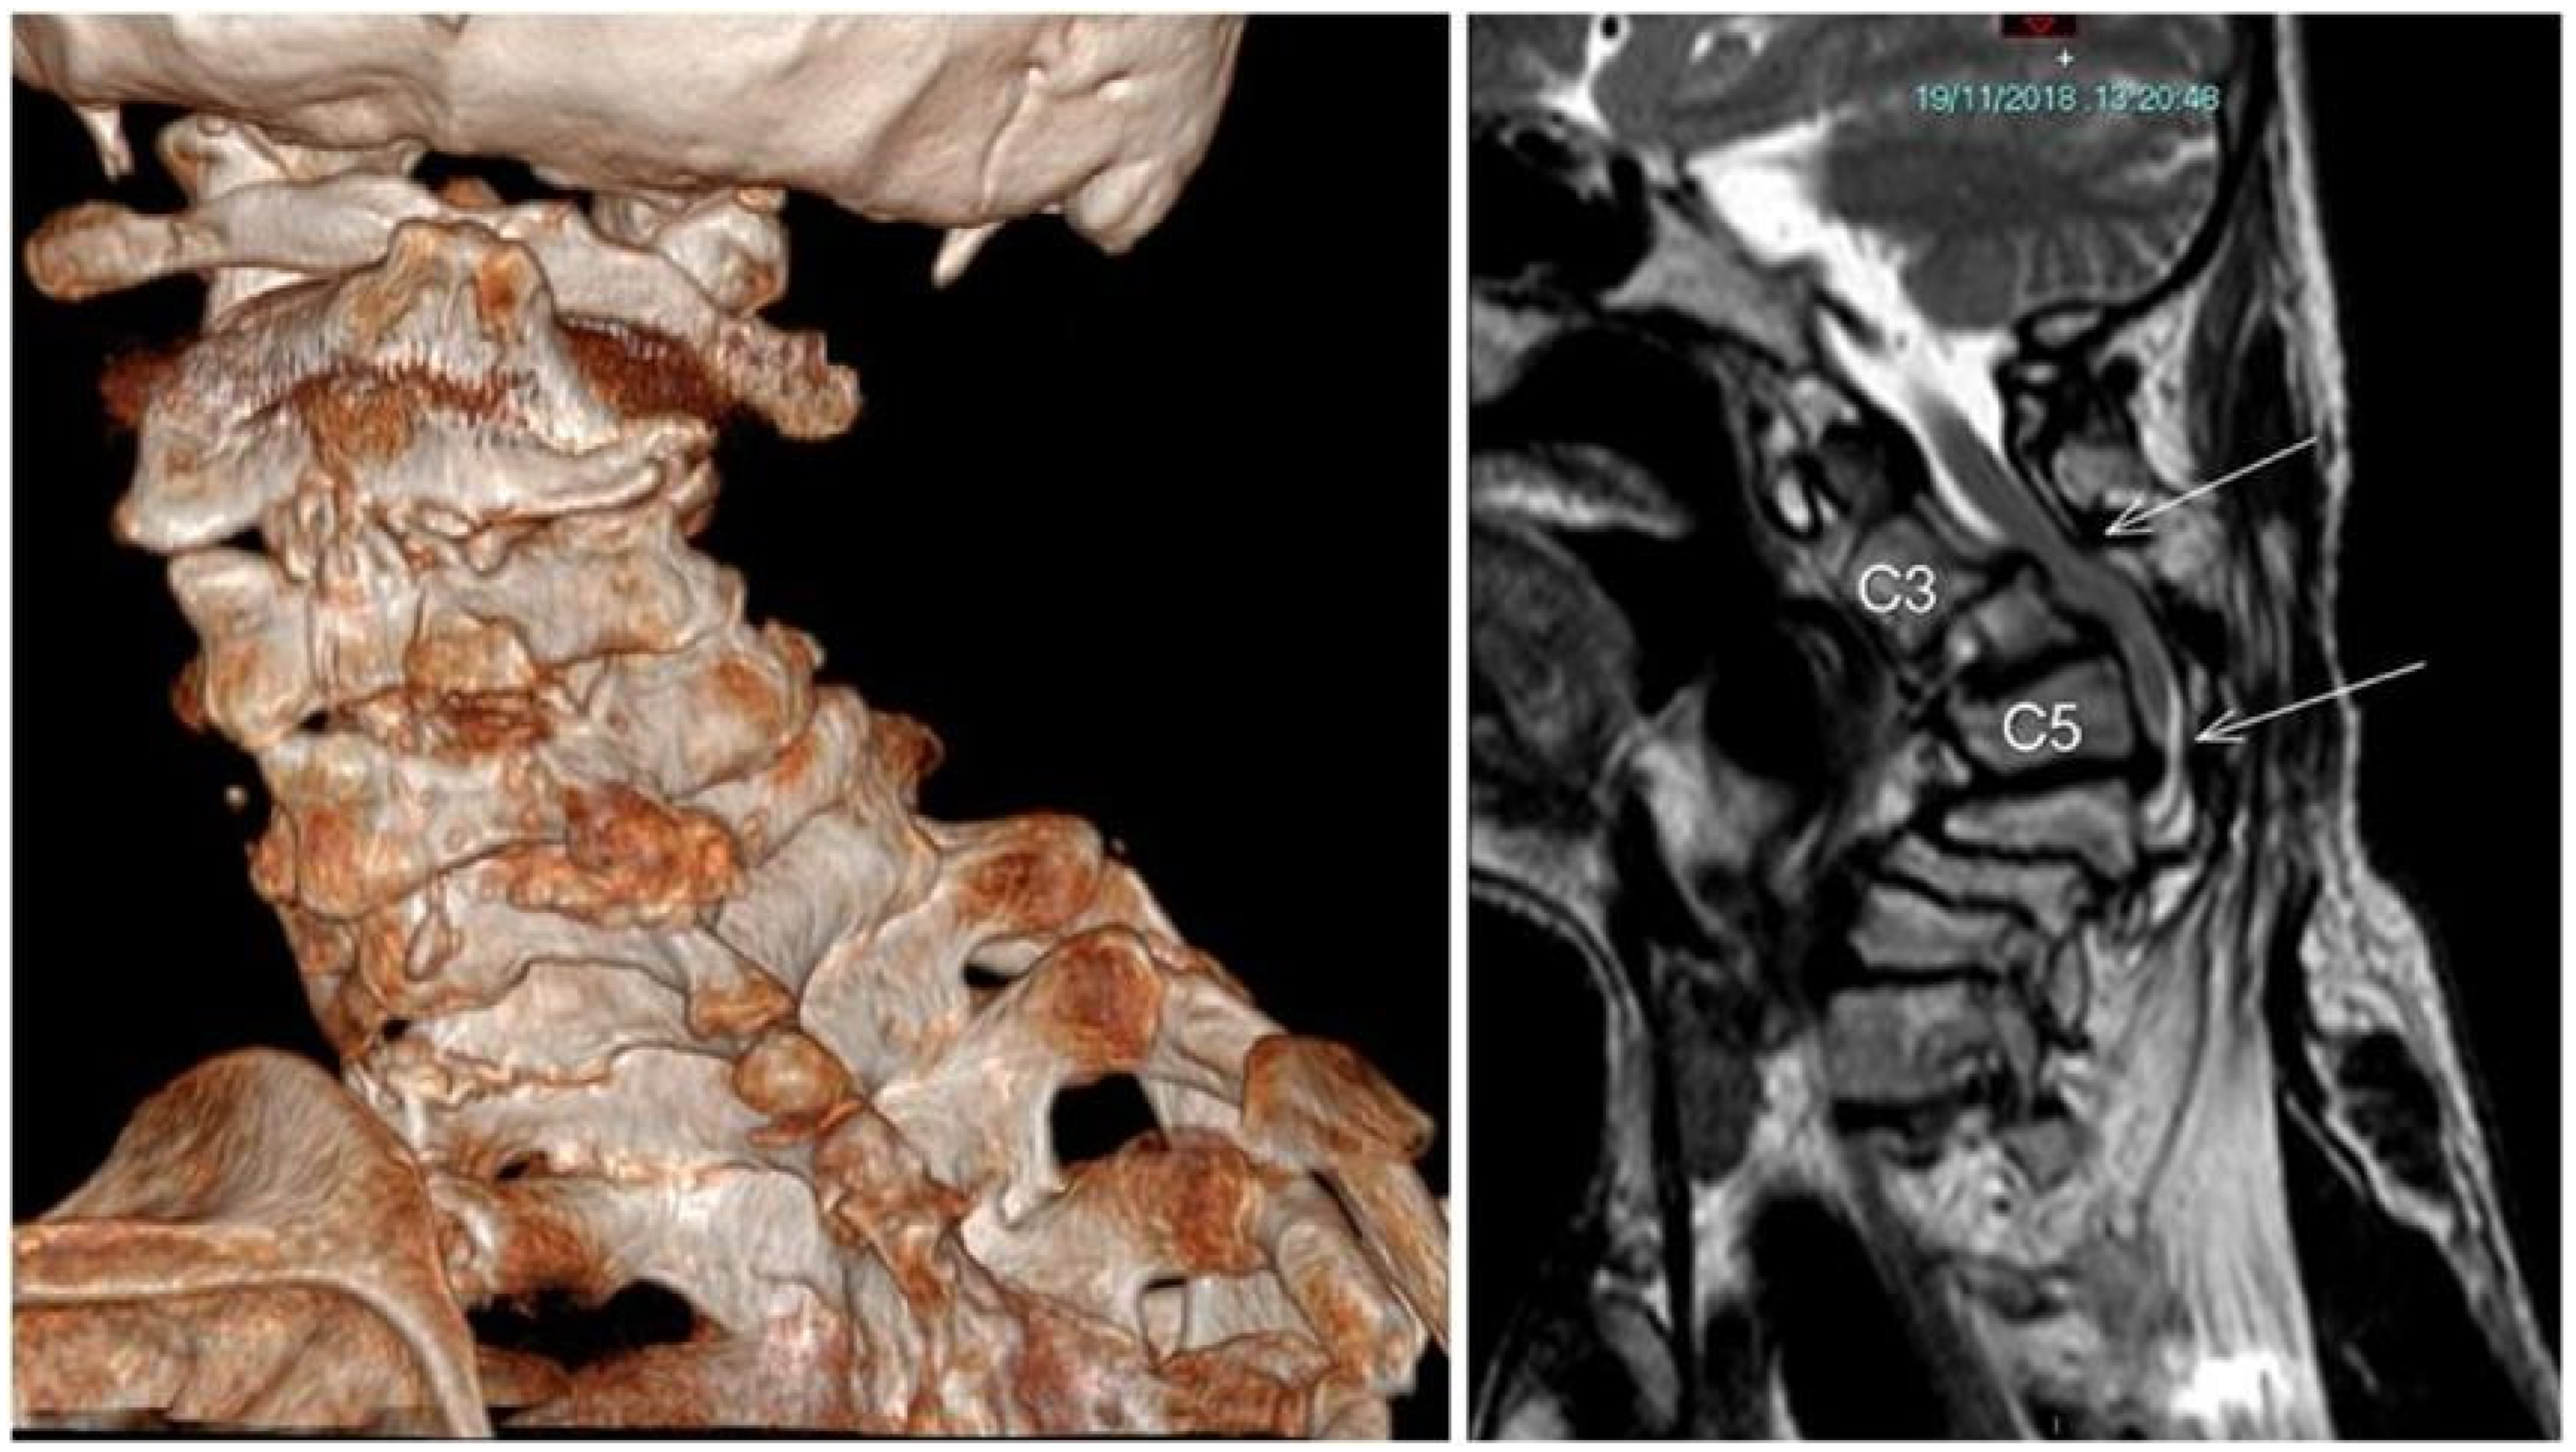

2. Case Description

Patient Details